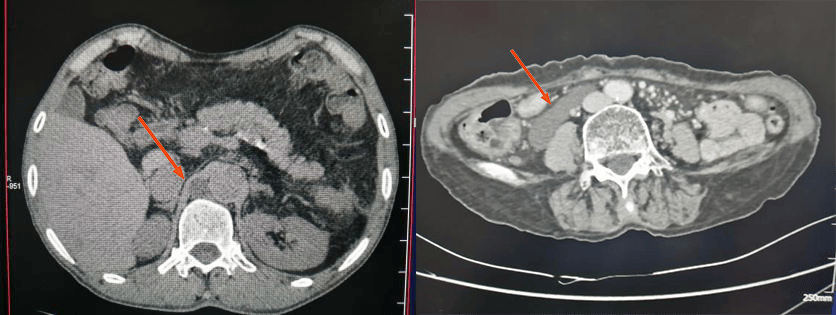

腹膜后脂肪肉瘤(位于右肾旁前间隙,肾脏及肾周脂肪受压向后内侧移位,升结肠和胰头受压向前内侧移位)。肿瘤以实性成分为主,内部及边缘部可见脂肪低密度影